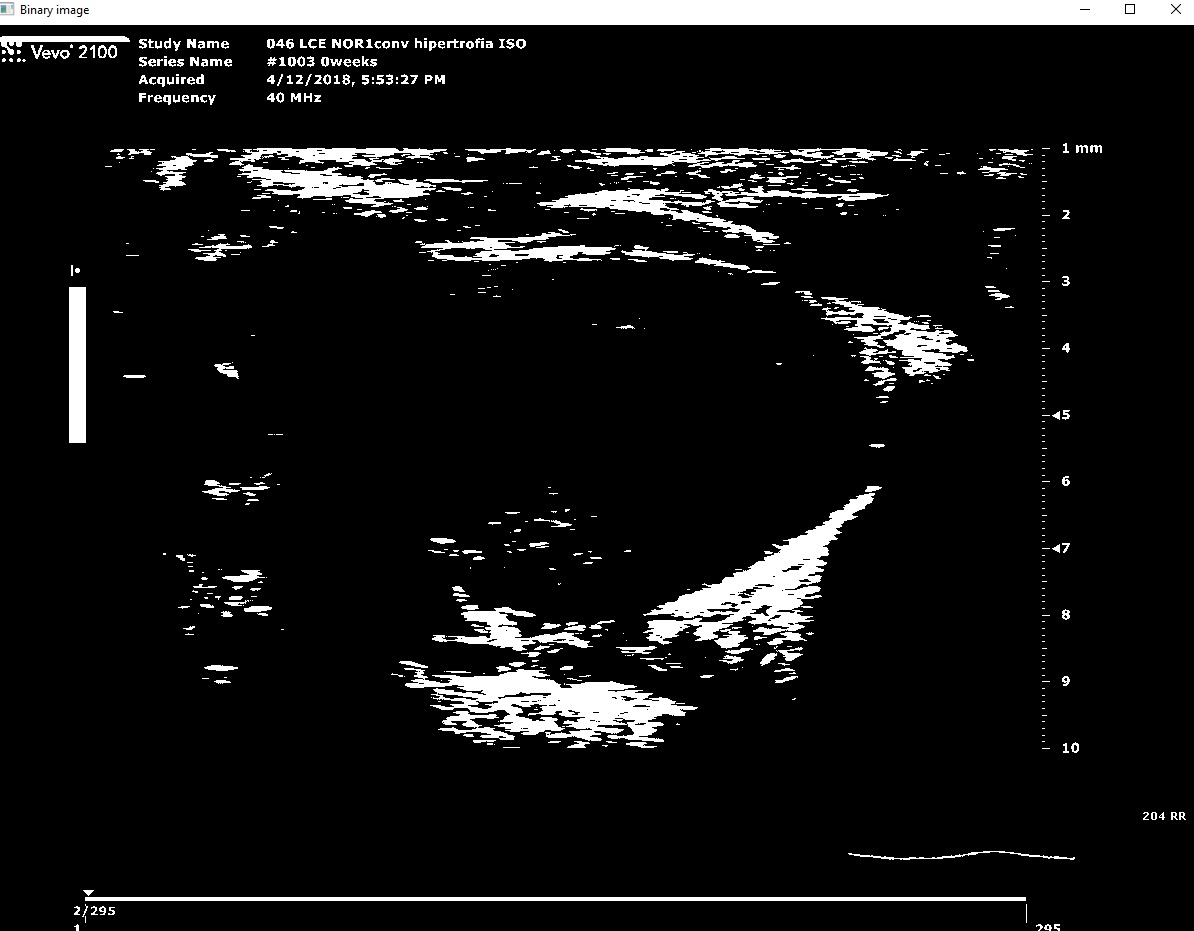

Its a CLI's program where have to give a psla and sax dicom files path. Then gets some variables from the files to throw some conclusions (if it's a healthy heart or not) and also it save it as excel file.

We built it as a python project with its virtual environment with the requirements needed, also needs a special program called Theseract that it is a optical character recognition open source to get the BPM from the files, the rest of the needed parameters are calculed using opencv mainly.

The most significative challenge that the team ran into consisted in the identification of the contourns of the image. Differenciating between the underside and the outer layer of the blood vessel ended up being an arduous task